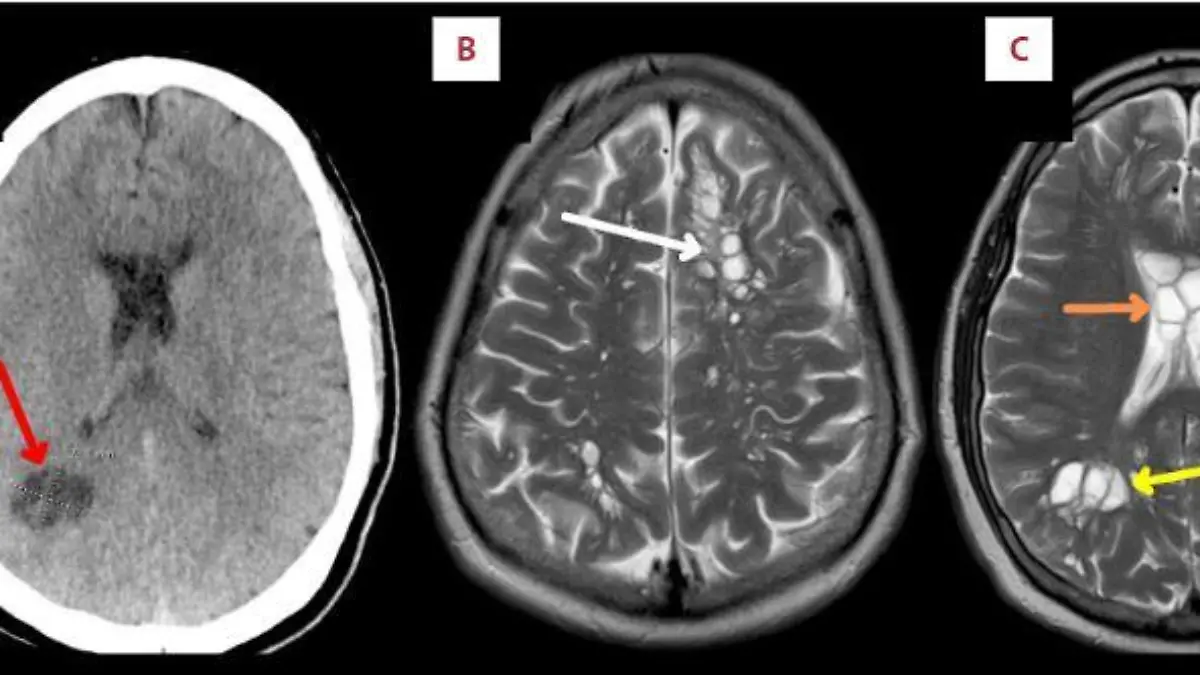

Über Monate klagte ein Mann aus Florida über Kopfschmerzen. Die Aufnahmen einer Computer-Tomographie zeigten schließlich den ekligen Grund dafür. Im Gehirn des Amerikaners hatten sich die Larven eines Schweinebandwurms eingenistet.

Schließlich ging der US-Amerikaner in ein Krankenhaus. Auf den CT-Bildern erkennen die Ärzte schließlich den Grund für die anhaltenden Schmerzen. In beiden Gehirnhälften hatten sich die Larven des Schweinebandwurms eingenistet. Mediziner sprechen von einer Zystizerkose.

In westlichen Ländern infizieren sich Menschen nur sehr selten mit dem Schweinebandwurm. Möglich ist das aber durch den Verzehr von verunreinigtem und nicht ausreichend gegartem Schweinefleisch. Im Fall des Amerikaners ist laut der Ärzte der nicht durchgebratene Speck zum Frühstück Überträger der Parasiten. Ansiedeln können die sich dann überall im Körper.

Der Mann wurde mit einem Entwurmungsmittel und entzündungshemmenden Medikamenten behandelt. Nach zwei Wochen ging es ihm besser. Von Mensch zu Mensch übertragen kann sich der Schweinebandwurm nur über eine Infektion im Darmbereich und mangelnde Hygiene im Umgang damit. (lra)